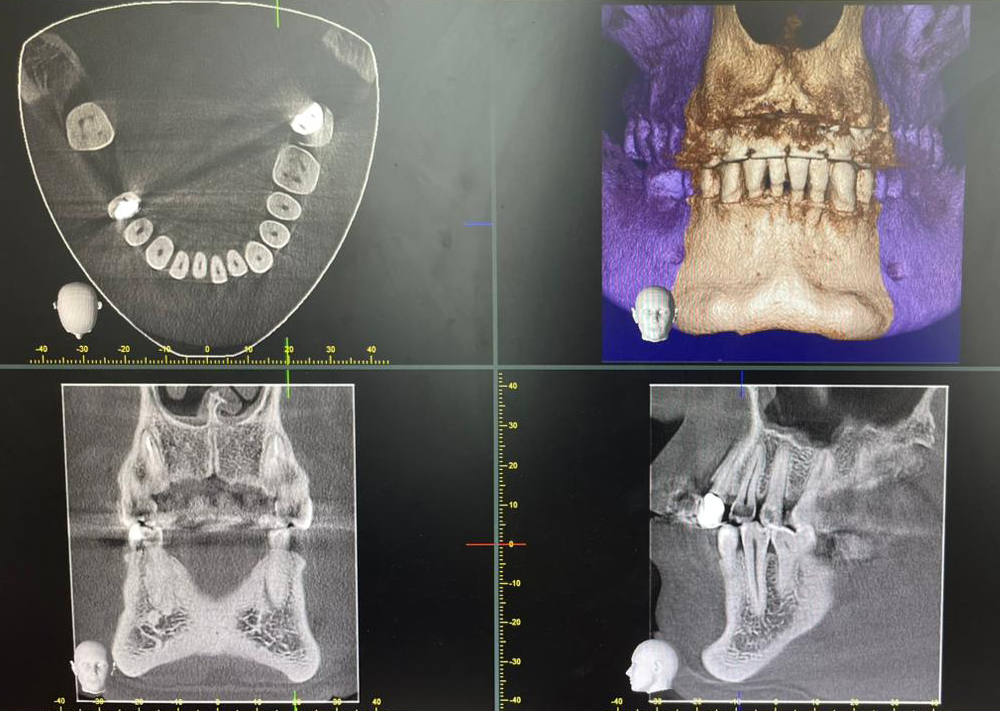

Сучасна рентгенологічна система Veraviewepocs 3D від компанії Morita поєднує три види знімків в одному апараті: панорамний, цефалометричний та 3D КТ (конусно-променеву томографію). Це дозволяє лікарю отримати максимально точне зображення зубів, щелеп та навколишніх структур для детальної діагностики і планування лікування.

• Точне 3D-зображення усіх анатомічних структур, включно з коренями зубів, каналами, кістковою тканиною та верхньощелепними пазухами.

Veraviewepocs 3D використовується для імплантології, ендодонтичного лікування, ортодонтії, хірургії та складних діагностичних випадків. Це надійний інструмент, який допомагає лікарю бачити найдрібніші деталі і приймати точні клінічні рішення.